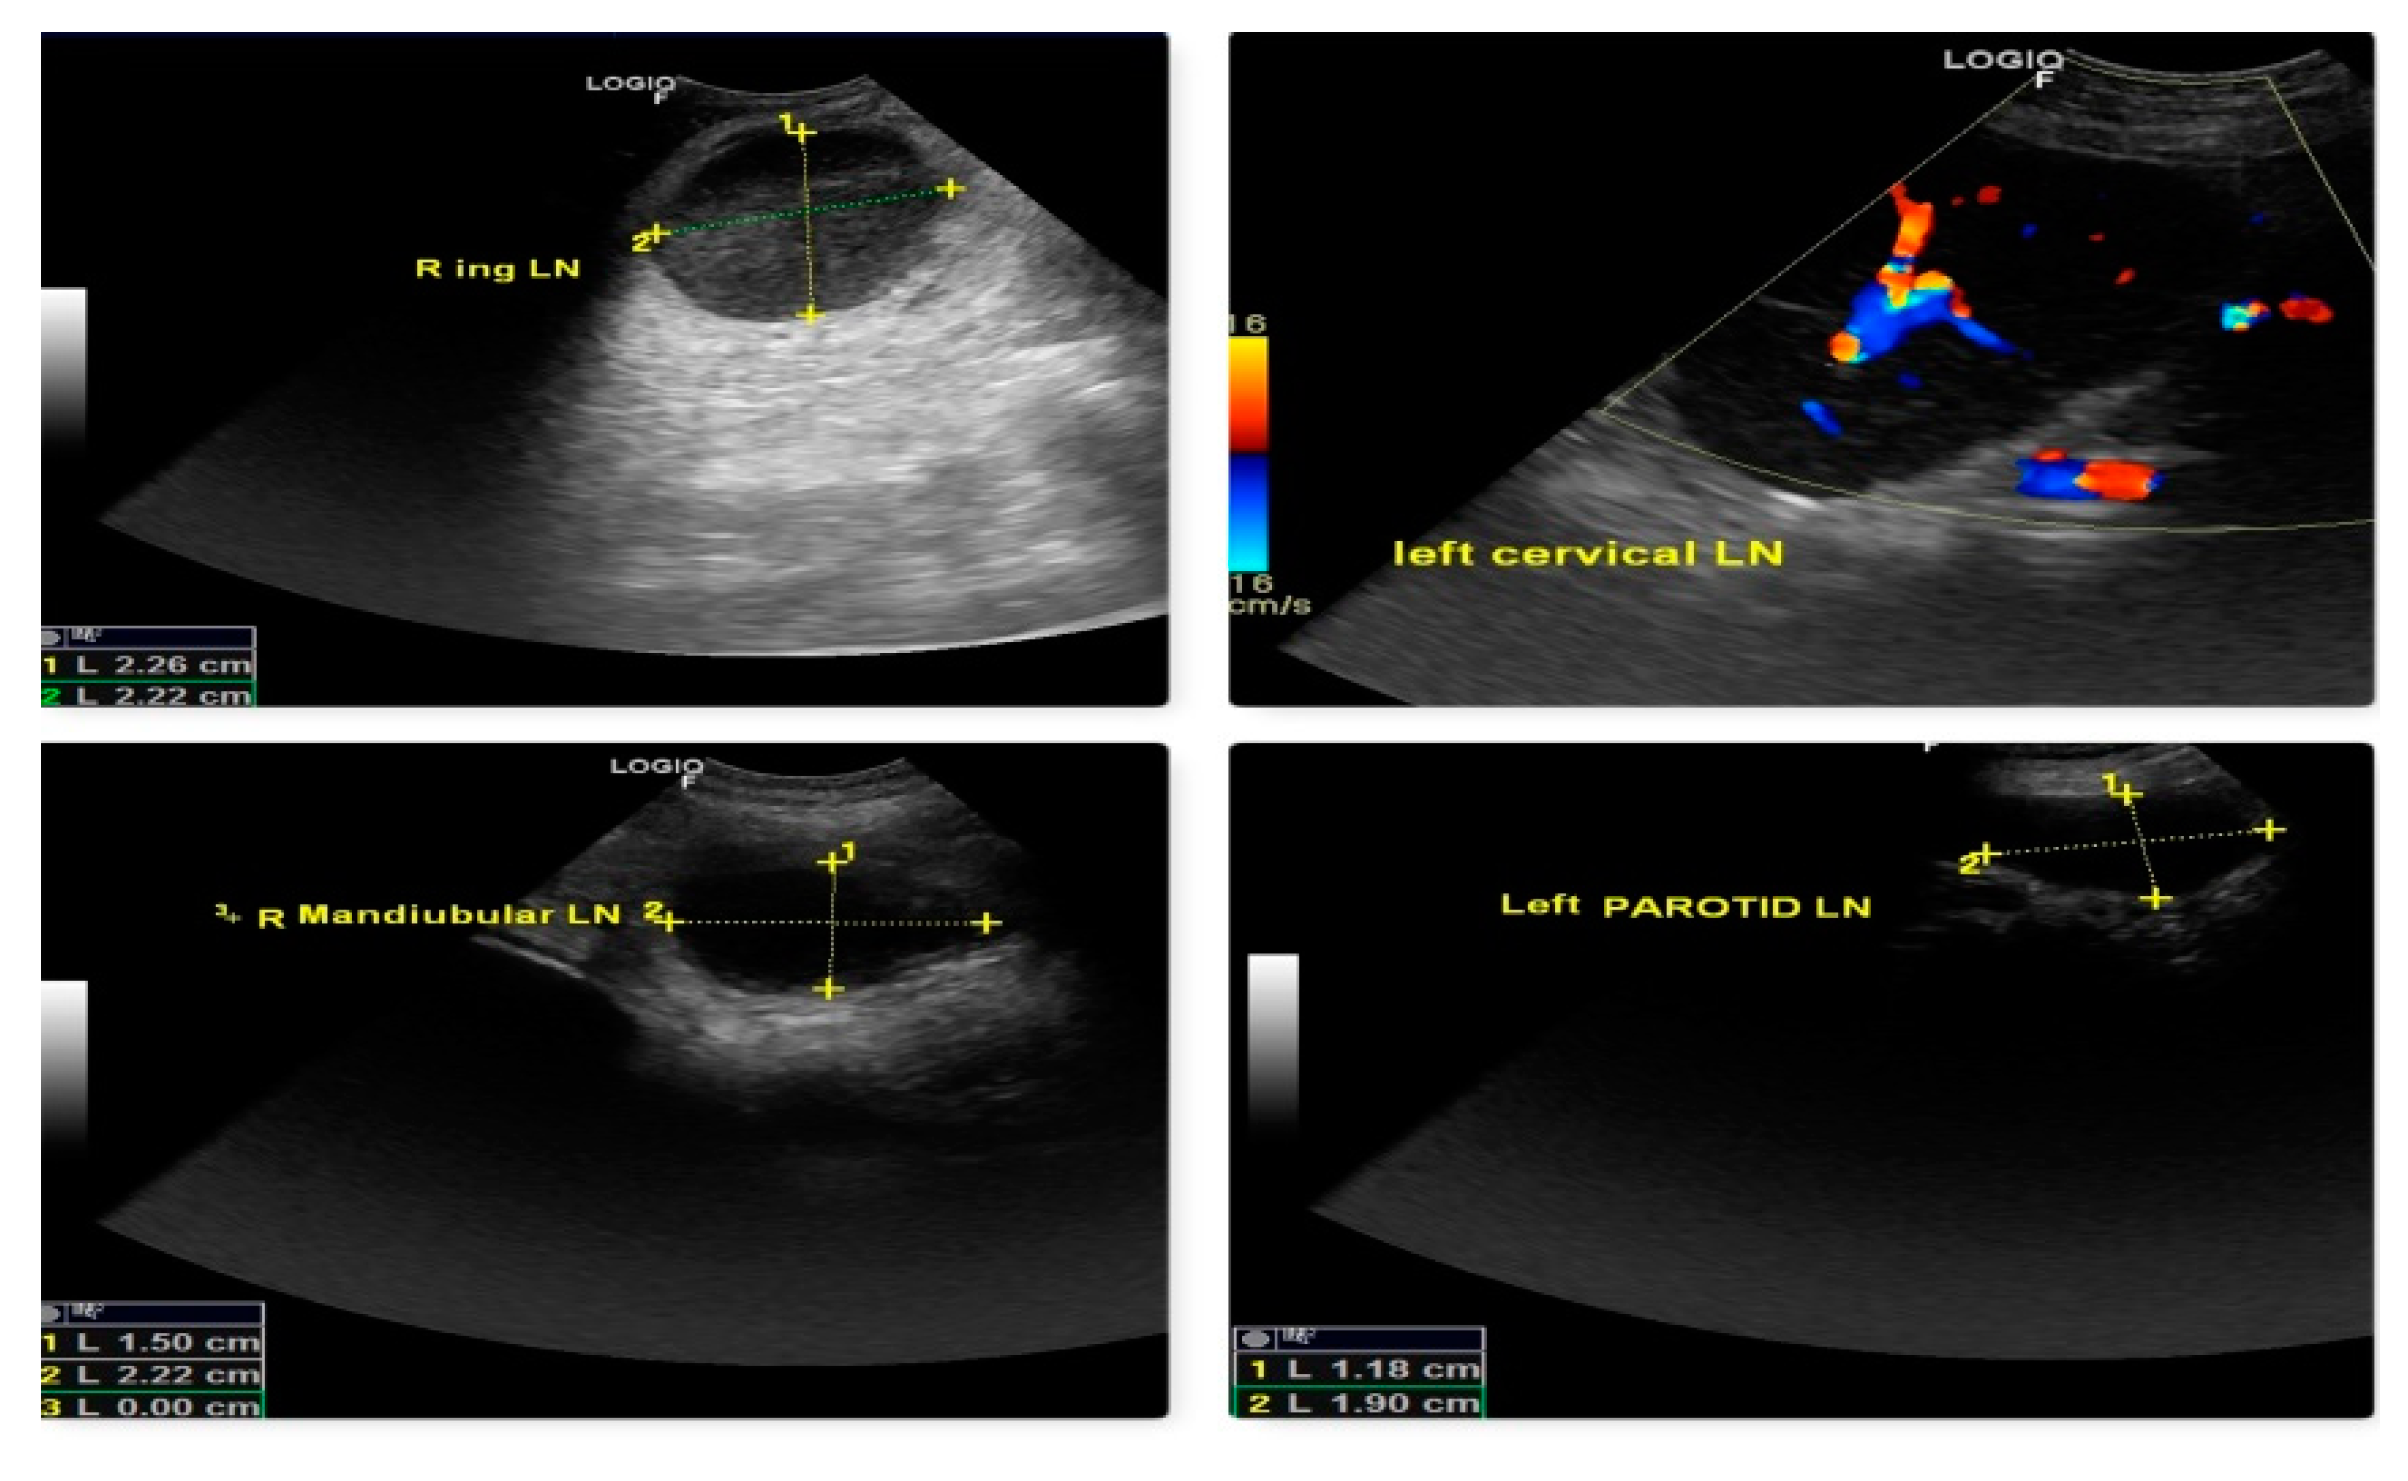

The malignancy criteria of the peripheral LN (submandibular, parotid, cervical, axillary, inguinal, and popliteal LN) were clearly described by ultrasonography. These criteria include oval form with S/L ratio 1, peripheral and central vascularization, and hypoechoic nodes as shown in Fig. 10, which are confirmed by cytology and biopsy. In the case of a primary tumor mass (lymphoma at 3rd molar) in the mouth cavity, mandibular LN were recognized as SLN within 2 minutes of indirect CT lymphography with iohexol. All superficial LN were found to have metastasized in lymphosarcoma which was a poor predictor of survival time.

Figure 10. Malignant changes observed through B-mode USG and color Doppler as generalized lymphedema (hypoechoic texture with S/L ratio ≤ 1, peripheral and central vascularization) in lymphosarcoma (ocular form).

Preprints 77141 g010